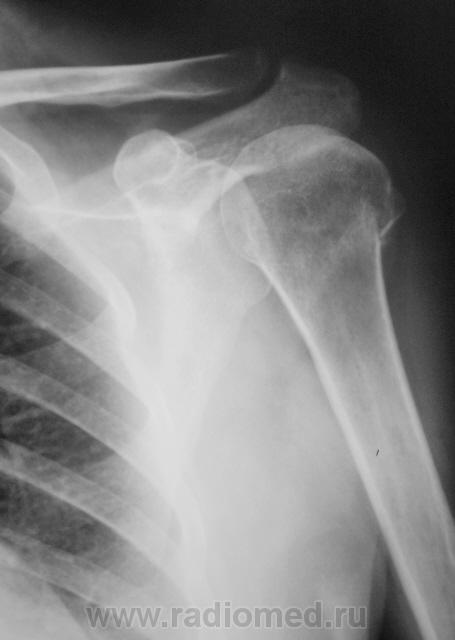

Валентин Львович, сколько ему лет?

18 лет.

Всё равно мне не очень понятно, что в костно-мозговом канале от в/тр диафиза до головки, не маленькая зона нарушения трофики, это и смутило. Моя ошибка, что возраст не узнал. А метастаз будет выглядеть аналогично. Травма не смущает, у 90% патологических переломов травма в анамнезе. Много таких было, очень много, поэтому и смущает всё и всегда.